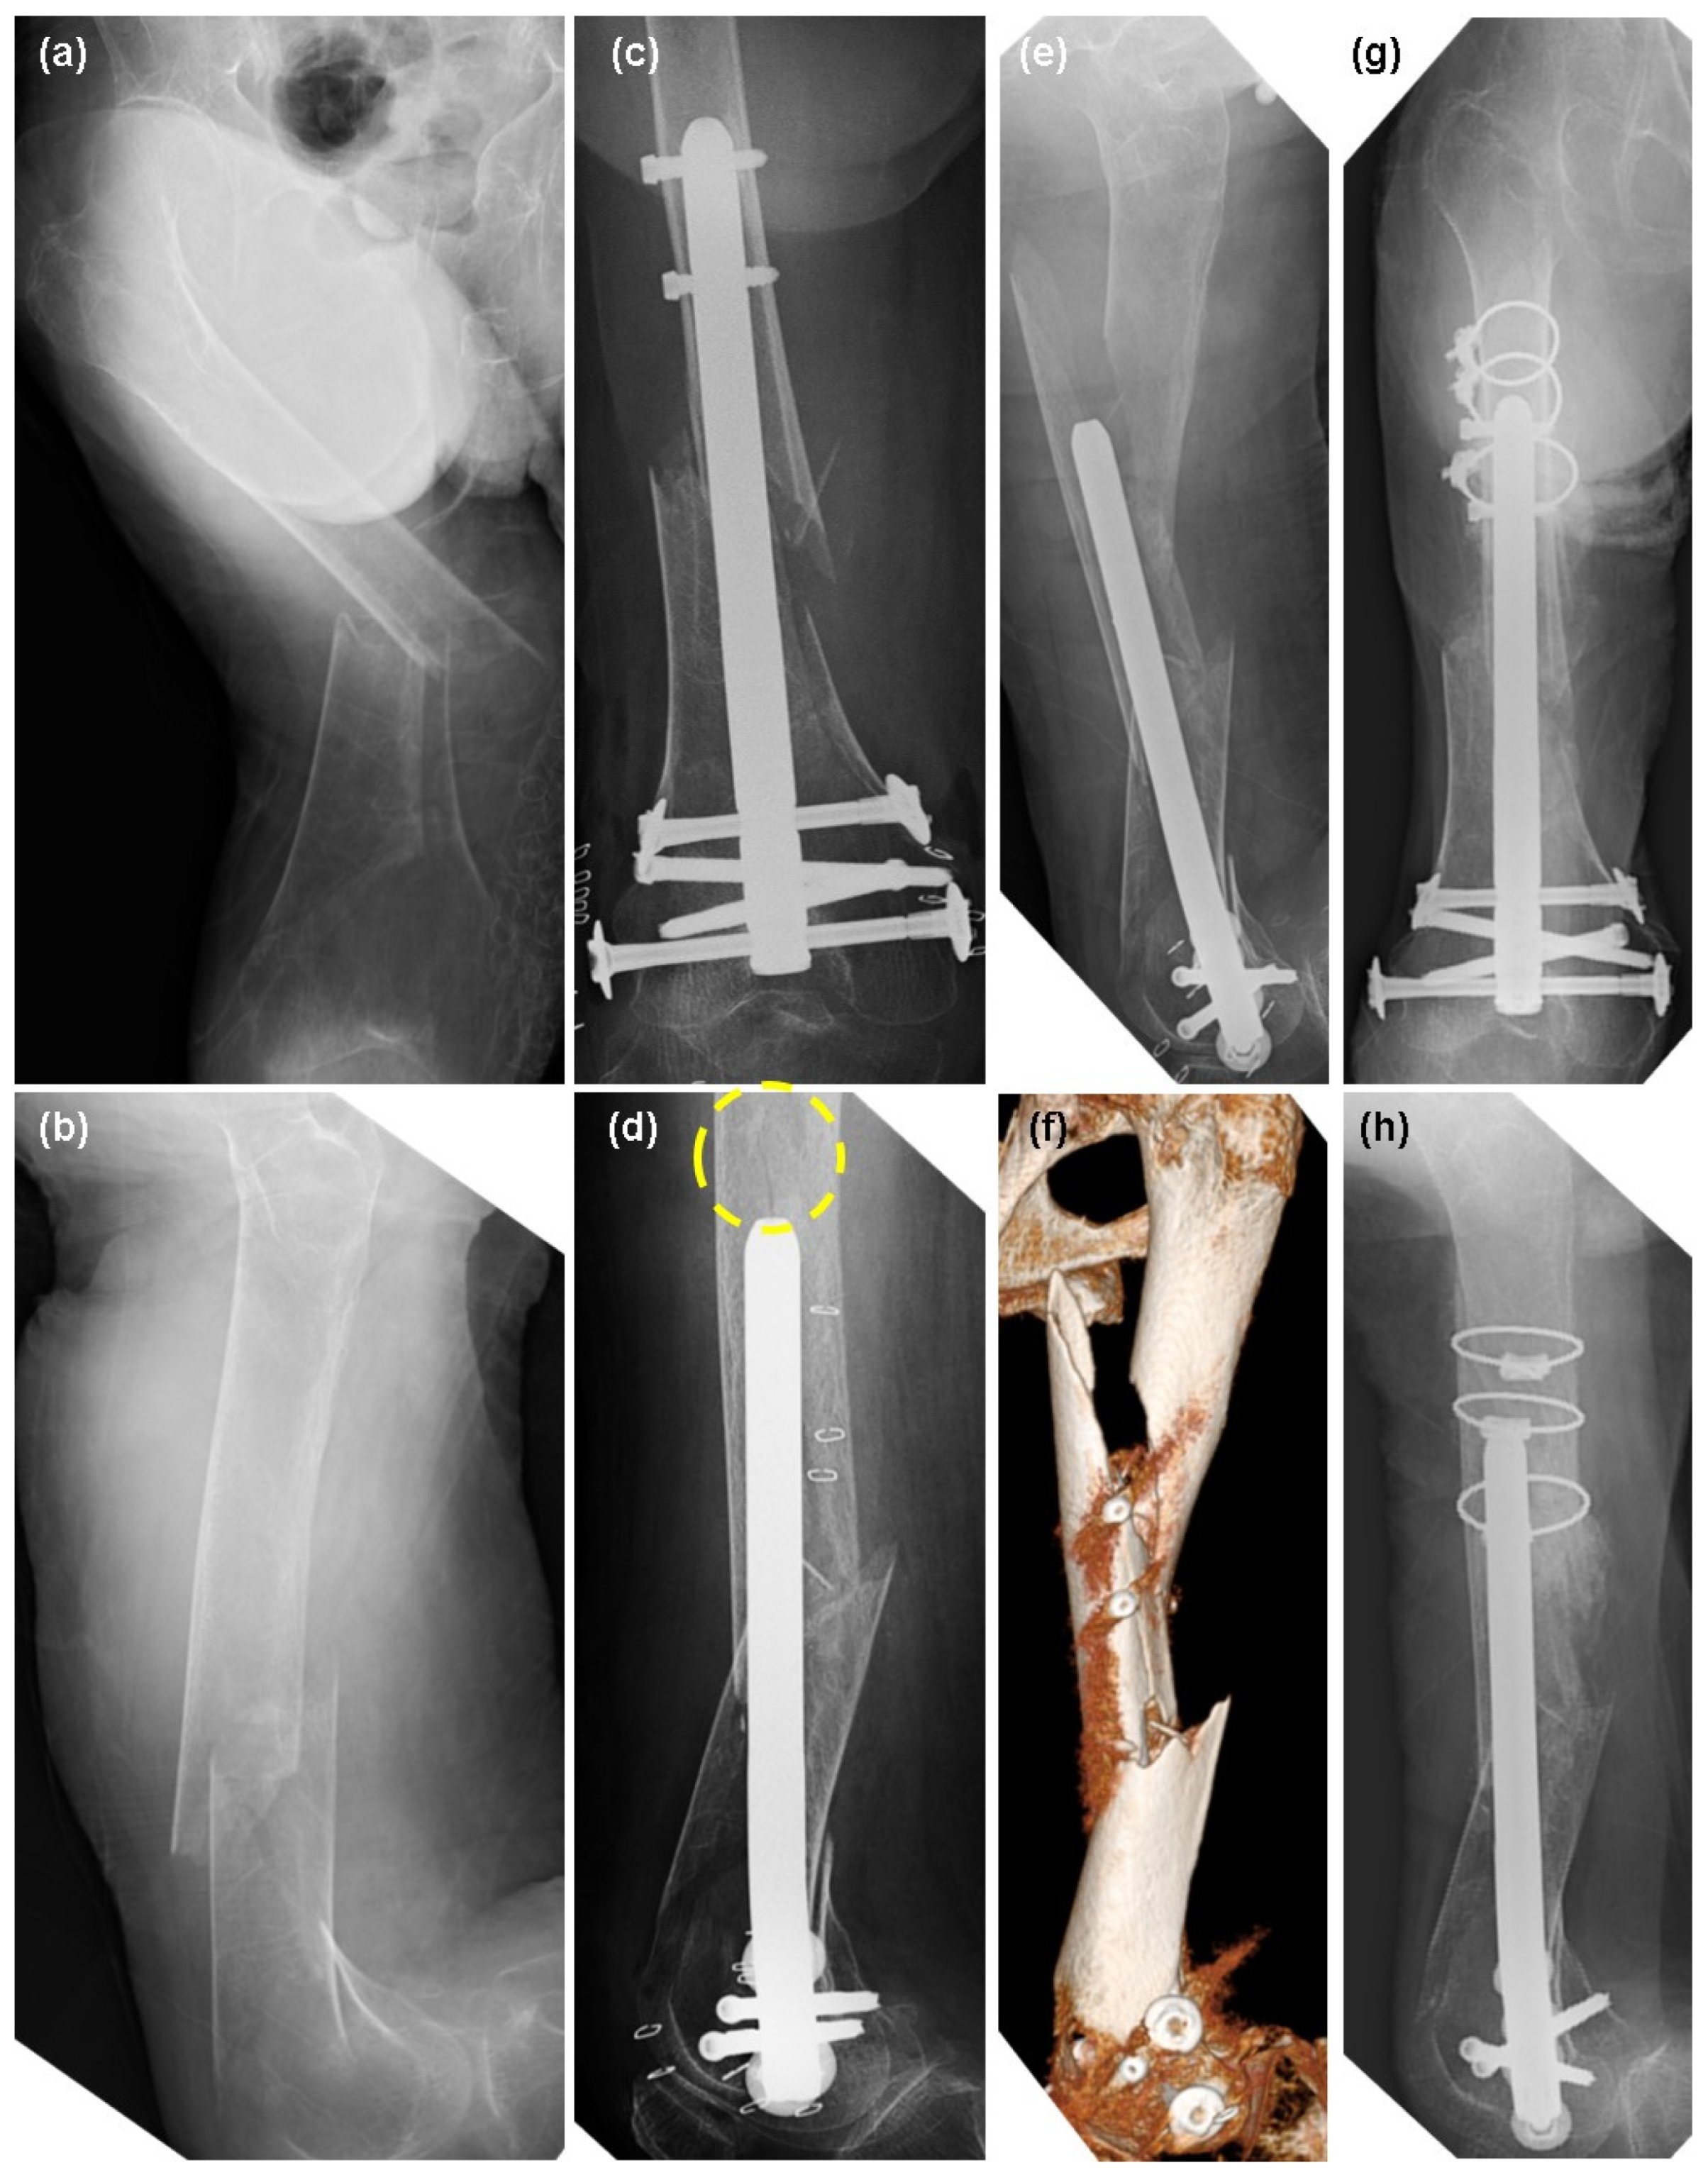

2.2. Patient 2